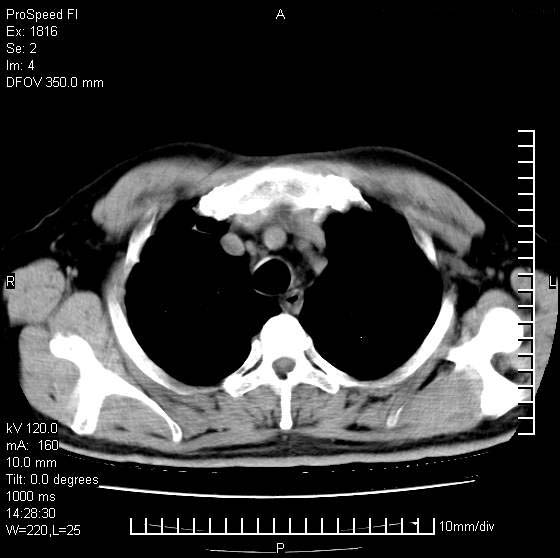

男性,50 ,肺结核9年,咳嗽,胸痛一周。右上肺见一厚壁空洞,周边有点样钙化,胸膜牵拉,洞壁较光整。诊断结核性空洞。有癌性的可能吗? 余肺野无异常,没有上传。

洞壁较厚内壁比较光整,两个病灶有关联性,纵隔淋巴结不大,考虑结核性空洞。

结核有可能,肺癌待排。空洞的前上还方见一软组织结节影。

部分层面见空洞为近似新月形,洞壁内缘尚规整且近肺门侧,周围见索条影、卫星灶,结合病史,首先考虑肺tb可能大。

右肺上叶为两个病灶,前面为陈旧型结核灶,其后方病灶像肺脓肿

9年的结核应该呈现多形态病灶,该病例只能见到少许纤维索条影,似乎与结核的演变不太相符。空洞内壁不光整,外侧伴有胸膜粘连,考虑癌性空洞可能性大,期待结果。